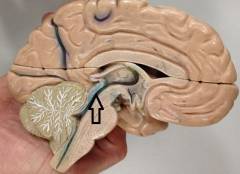

В норме головной мозг окружен спинномозговой жидкостью. Она заполняет его внутренние полости, – мозговые желудочки, — а также пространство вокруг него.

Образование спинномозговой жидкости происходит главным образом за счет множества мелких сосудов, расположенных в стенках мозговых желудочков. Каждую минуту у взрослого человека вырабатывается примерно 0,35 мл спинномозговой жидкости, а за сутки – около 500 мл. Такое же её количество должно всосаться в вены головного мозга. Так постоянно происходит её обновление.

Гидроцефалия развивается в том случае, когда возникает несоответствие между количеством вырабатывающейся и всасывающейся спинномозговой жидкости. Это может происходить в силу разных причин.

Внутренняя – спинномозговая жидкость скапливается внутри желудочков мозга.